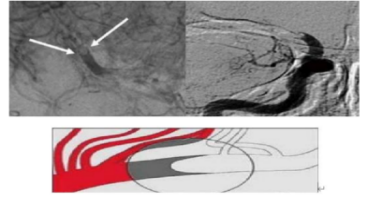

微导管首过效应 微导管首过效应是判定 ICAS 病变的重要方法。在微导丝和微导管通过闭塞段后,保留微导丝,回撤微导管到闭塞段近端(不完全撤出),造影即可显示前向血流恢复,通过闭塞段显示远端血管分支完整,即为首过效应阳性。

血管动脉粥样硬化原位狭窄的基础上急性血栓闭塞(ICAS 病变),血管狭窄的基础上急性血栓形成。

主要原因:心脏血栓、血管通路斑块脱落卡顿于狭窄部位、狭窄部位的斑块破裂血小板聚集形成血栓,血栓负荷往往较小,微导丝、微导管通过闭塞后血管再通,首过效应阳性。

ICAS 基础上的血管闭塞具备这些特点:

①血栓负荷量相对较小,微导管首过效应阳性率高;

②血管开通后容易出现再次闭塞;

③多次取栓后会出现血管损伤、继发血栓形成、动脉夹层或者远端血流越来越差等情况。

微导丝微导管首过效应阳性、支架取栓释放后呈现“束腰征”。

术中操作:由于血栓负荷较小,支架半收拢回撤,防止损伤狭窄血管内壁或球囊扩张。